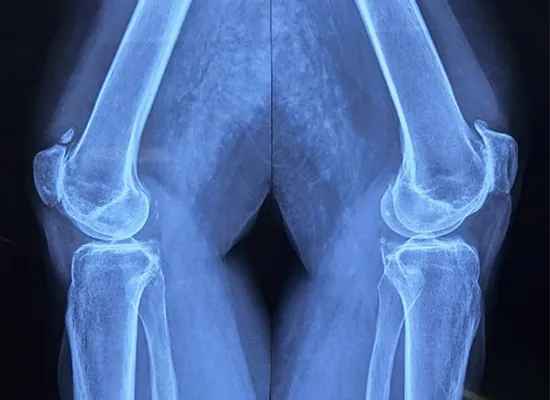

Imaging preoperativ

1

View AP ki montre gwo rediksyon espas jwenti

Imaj apre operasyon

4

View AP ki montre bon aliyman implant

5

View lateral demontre gerizon zo